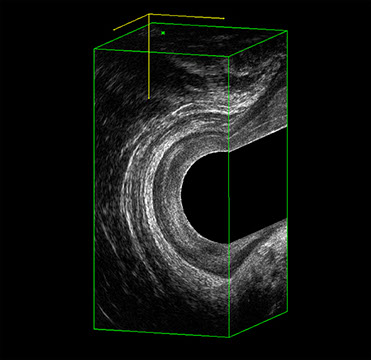

Proctal dispone di apparecchiatura per ecografia endoanale 3D con sonda rotante.

Sezione Longitudinale 3D con Tramite Fistoloso Intersfinterico Basso Anteriore Semplice